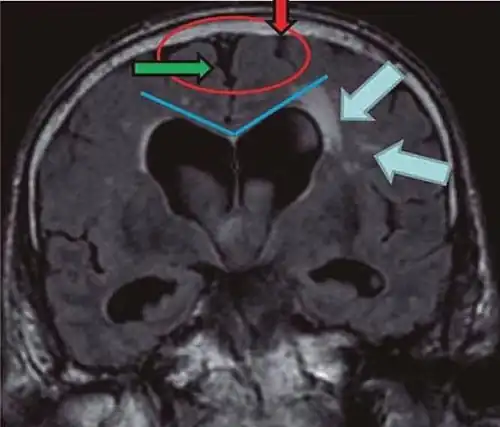

Typical imaging findings in normal pressure hydrocephalus versus brain atrophy.[21]

Normal pressure hydrocephalus Brain atrophy

Preferable projection Coronal plane at the level of the posterior commissure of the brain.

Modality in this example CT MRI

CSF spaces over the convexity near the vertex (red ellipse ) Narrowed convexity ("tight convexity") as well as medial cisterns Widened vertex (red arrow) and medial cisterns (green arrow)

Callosal angle (blue V) Acute angle Obtuse angle

Most likely cause of leucoaraiosis (periventricular signal alterations, blue arrows ) Transependymal cerebrospinal fluid diapedesis Vascular encephalopathy, in this case suggested by unilateral occurrence